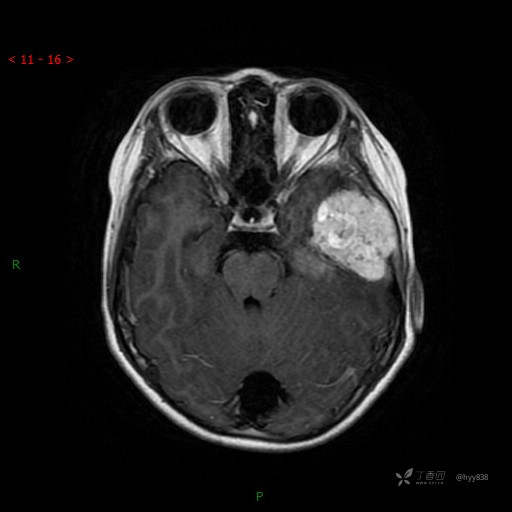

“典藏”病例分享。10岁儿童,头痛头晕一周余,CT、MRI 都有---结果公布~

简要病史:患者于一周前无明显诱因开始出现头痛头晕,无恶心呕吐,无肢体抽搐,无寒颤高热,无腹胀腹泻,无视力下降及视野缺损,上述症状休息后可稍缓解,未引起重视。 2天前患者头痛头晕不适加重,伴有恶心感,无呕吐,遂到当地人民医院行头颅CT检查示:左侧颞部占位性病变,今日家属为求进一步治疗,来我院门诊求治。门诊拟“左侧颞部占位性病变”收入我科。 患病以来,患者精神、饮食、睡眠尚欠佳,大小便如常,体力体重无明显变化。

临床诊断:左侧颞部占位

MRI增强